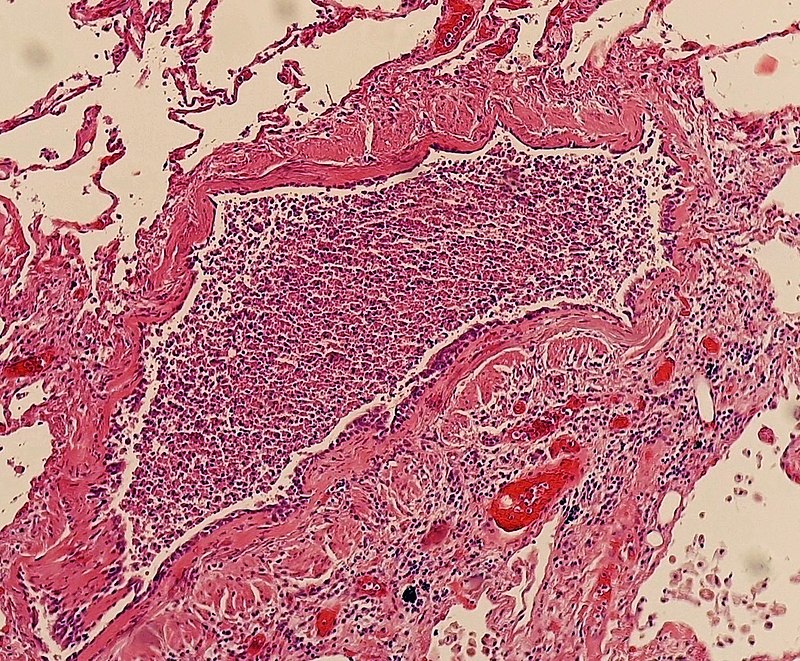

Tuberculosis (TB)

Tuberculosis (TB) results in the hilar lymph nodes undergoing fibrosis and calcification to produce a Ghon complex as well as localized, caseating necrosis of the lung.

Tuberculosis (TB) creates a cavitary foci of caseous necrosis and has the potential to cause tuberculous bronchopneumonia or miliary pulmonary tuberculosis.

Histology of tuberculosis (TB) shows caseating granulomas, and positive acid-fast bacilli (AFB) stain.